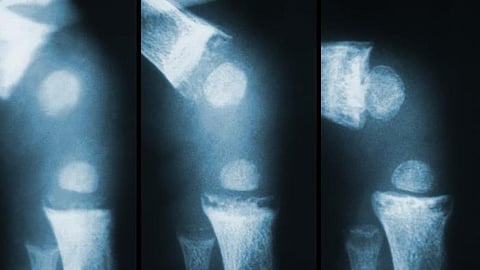

Doctors conducted an experiment involving a series of patients suffering from osteoarthritis of the knee joint with damage to one of the sections of the joint. All patients underwent surgical correction of the limb. Six weeks after the operation, half of the patients were injected with platelet-rich plasma (PRP) into the knee joint, the other half received stromal vascular fraction (SVF), their own stem cells from adipose tissue with regenerative potential. Doctors continued to monitor patients for a year and a half. RUDN doctors monitored the level of pain and functional activity.

Those patients who received platelet-rich plasma showed a slightly better result, visible only on the KOOS, KSS and VAS scores. The first two evaluate the function of the knee joint and the activity of the patient, the last measures the intensity of pain. In patients who were injected with stem cells, they also received good results on clinical and functional scores and the best indicators in terms of the degree of regeneration of destroyed joint tissues (articular cartilage). The physicians concluded that both options can be considered as improving the results of the technique for stimulating tissue regeneration after osteotomy.